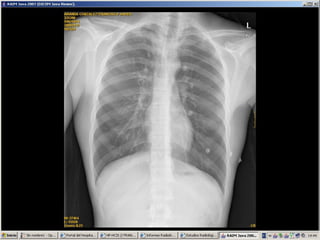

Rx Tórax

   Aire pericárdico, delimitación de los

grandes vasos y del mediastino.

   Lateral (suele ser más adecuada para el

diagnóstico):

 Cantidades variables de aire en mediastino

anterior,

 Alrededor de aorta ascendente,

 Enfisema subcutáneo.

Rx Tórax  Aire pericárdico, delimitación de los grandes vasos y del mediastino.  Lateral (suele ser más adecuada para el diagnóstico):  Cantidades variables de aire en mediastino anterior,  Alrededor de aorta ascendente,  Enfisema subcutáneo.